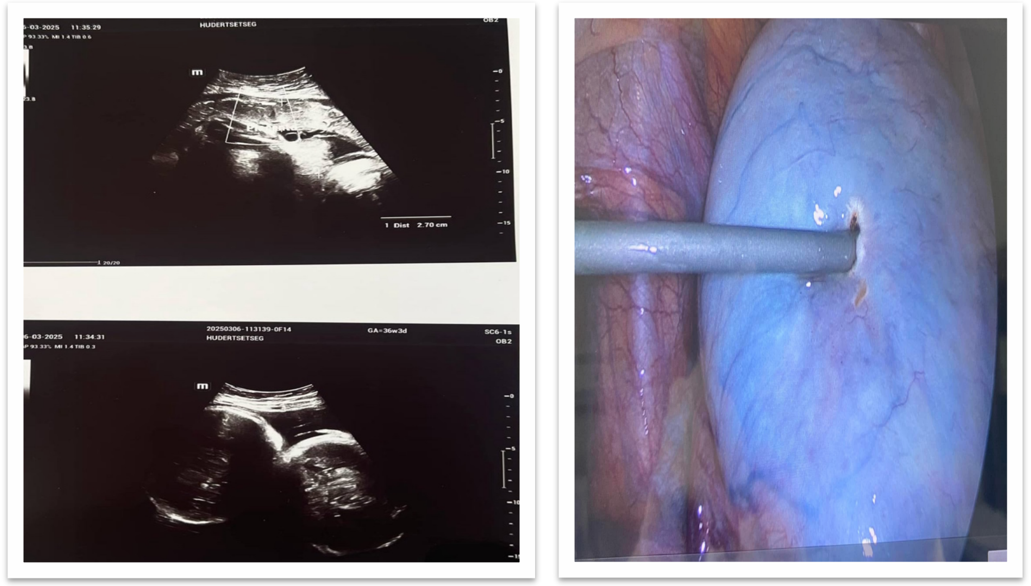

Figure 2: Ultrasound image Figure 3: The surgical procedure

Diagnostic Assessment: Pelvic ultrasound demonstrated a multilocular mass measuring 13.6 × 10 × 9.7 cm with honeycomb- like septations and increased vascularity. Laboratory evaluation revealed an elevated CA-125 level (60 U/mL) and an elevated Inhibin B level (58.24 pg/mL); lactate dehydrogenase (LDH, 300 U/L) and alpha-fetoprotein (AFP, 4.9 U/mL) were within normal limits. Endoscopy and chest radiography showed no evidence of metastasis. Preoperative risk assessment using the International Ovarian Tumor Analysis (IOTA) criteria indicated a high malignant potential. The IOTA Simple Rules identified multilocularity, solid components, and increased vascularity as suspicious features, while the ADNEX model estimated a high probability of a borderline or malignant ovarian tumor.